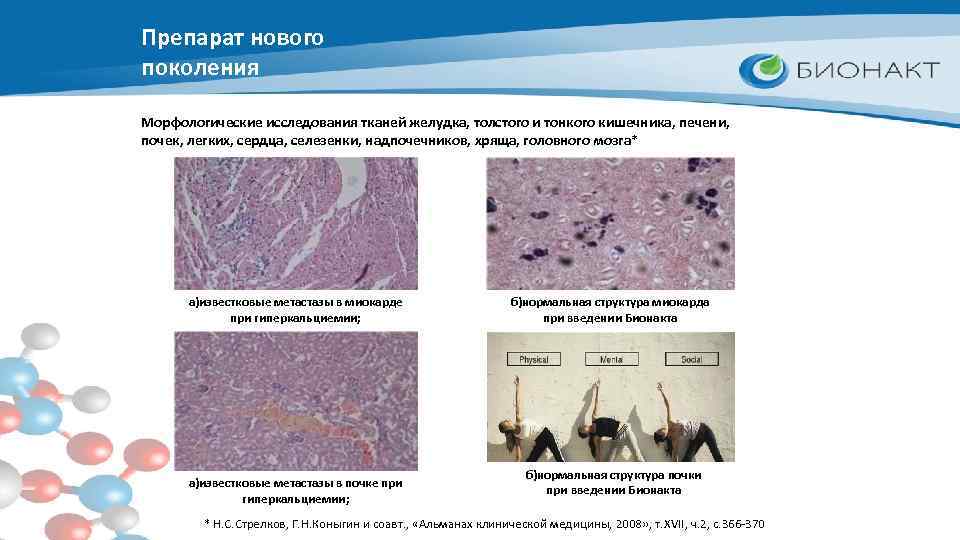

Препарат нового поколения Морфологические исследования тканей желудка, толстого и тонкого кишечника, печени, почек, легких, сердца, селезенки, надпочечников, хряща, головного мозга* а)известковые метастазы в миокарде при гиперкальциемии; а)известковые метастазы в почке при гиперкальциемии; б)нормальная структура миокарда при введении Бионакта б)нормальная структура почки при введении Бионакта * Н. С. Стрелков, Г. Н. Коныгин и соавт. , «Альманах клинической медицины, 2008» , т. XVII, ч. 2, с. 366 -370